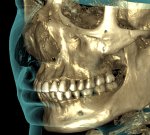

Сделал снимок своей челюсти, чтобы вам было лучше видно какой я унтерменш

>>331338129 (OP)

Дурак. Ты себя радиацией облучил.

Срочно выпей красного вина.

Че за бородавка костная нахуй? Ты че ваще нахуй?

изимодник с идеальными зубами чтоб ты сдох

ищо и денег есть на такой рентген, он тыщ 20 стоит наверняка

Чо восьмерочек слева не завезли?